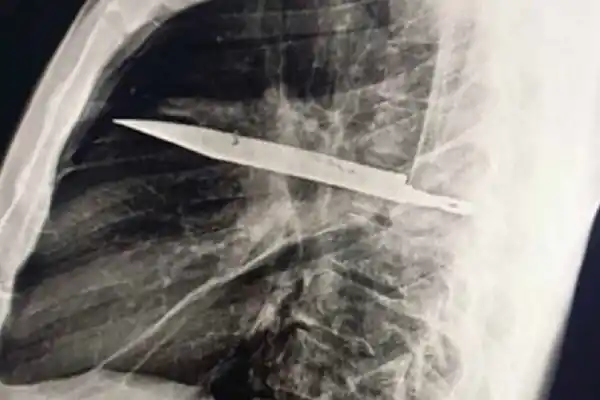

Impactante caso: un hombre llevó un cuchillo dentro del pecho durante casi una década

Durante casi una década, el paciente llevó una vida aparentemente normal, sin dolor torácico, dificultades respiratorias, tos ni fiebre.